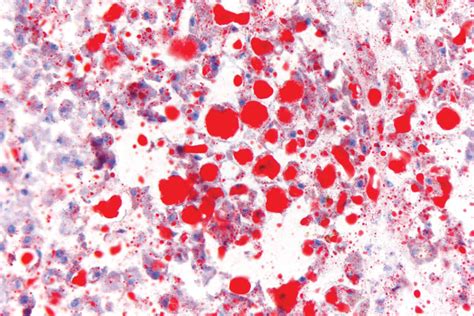

Interpreting Oil Red O Stained Sections

Interpreting Oil Red O stained sections requires careful examination under a microscope. The stained lipids appear bright red, while the background tissue may appear counterstained or unstained, depending on the use of a counterstain. Here are some key points to consider when interpreting the stained sections:

• Lipid droplet size and distribution: The size and distribution of lipid droplets can provide insights into lipid metabolism and storage. For example, large lipid droplets may indicate lipid overload, while small, dispersed droplets may suggest active lipid metabolism.

• Lipid accumulation in specific cell types: The technique allows for the visualization of lipid accumulation in specific cell types, such as adipocytes, hepatocytes, or macrophages. This can help identify the cellular sources of lipid accumulation in various pathological conditions.

• Quantification of lipid content: The intensity of the red stain can be quantified using image analysis software, allowing for the measurement of lipid content in tissues. This is useful for comparing lipid accumulation in different experimental conditions or disease states.

To enhance the interpretability of Oil Red O stained sections, it is recommended to use appropriate controls and positive stains. Controls can include unstained sections or sections stained with a different lipid stain, such as Sudan IV or Nile Red. Positive stains can include sections known to contain high levels of lipids, such as adipose tissue or liver tissue from obese animals.